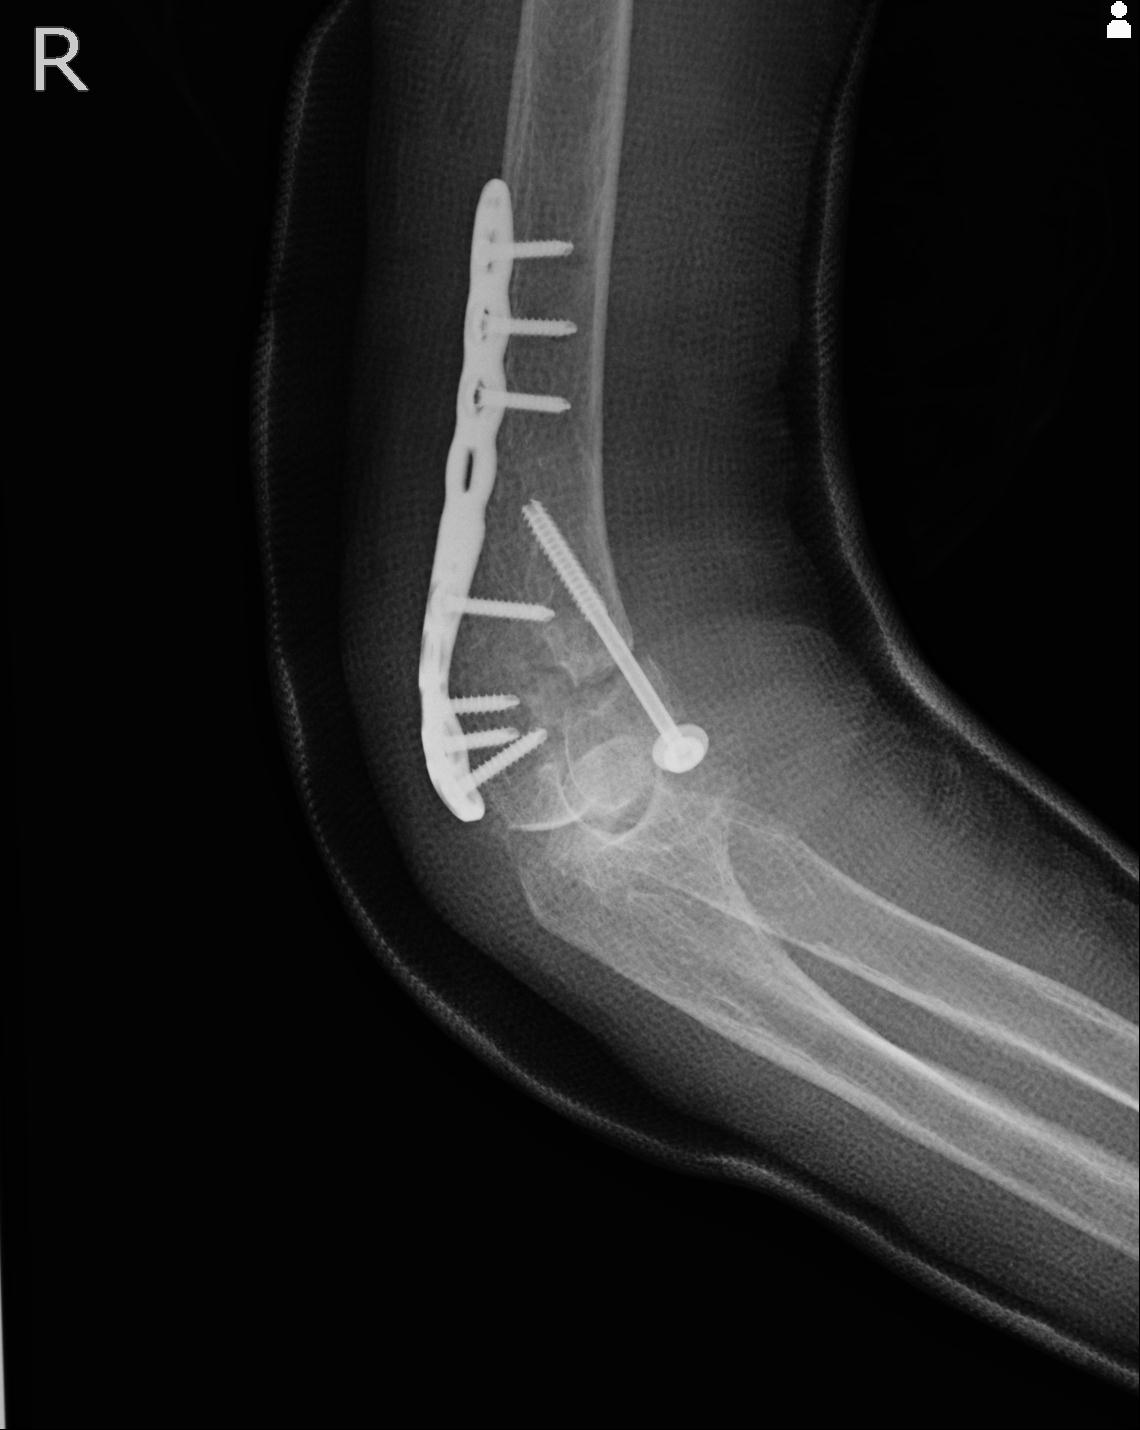

110214 12/20 肩 2R 12/21 肩 4R 72歳女性 左上腕外科頚プレート